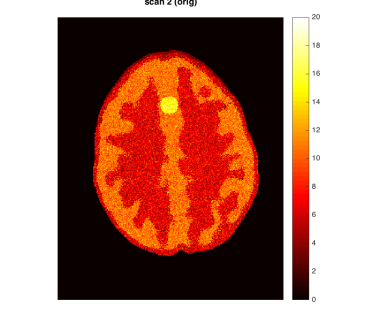

As a motivating example that will be detailed in Section 5, Figure 1 shows data from the phantom experiment in Qin et al., (2017) simulating pre- and post-treatment scans with a tumor lesion. A direct voxelwise difference between the two scans shows a global non-homogeneous background change while failing to detect changes in the lesion (Figure 1, Row 1 and Column 3). This observation suggests that background adjustment is necessary in voxelwise comparisons to reduce confounding by tissue-dependent changes not related to the disease, in order to isolate localized differences that are relevant to assess the disease status.

In the first half of this paper, we study the standardization of a Gaussian mixture model systematically in various but simple ways. We show that, surprisingly, the tail distribution of the standardized scores is favorably close to standard normal in a wide range of scenarios while being conservative at the tails, making it suitable for statistical inference. Compared to the standardization method for background adjustment in Guo et al., (2014) and Qin et al., (2017), we consider several variations using both soft and hard assignment of the observations to latent classes. In the data application in Figure 1, the analysis based on the model-based standardized differences proposed in this paper is successful (Row 2 and Column 3) as the background difference is now randomly distributed around zero and the lesion change is clearly visible; see Section 5 for more details. The distributions of the corresponding standardized scores are evaluated here theoretically, numerically and via simulations. Theoretically, it is shown that the standardized scores are indeed close to standard normal under a variety of extreme parameter settings. In non-extreme parameter settings, it is shown numerically that the soft assignment methods lead to conservative tail probabilities, making them valid for hypothesis testing purposes. It is also shown that the tail probabilities are not very sensitive to the class probabilities, which is an advantage as these are hard to estimate in practice.

In this section, we provide more details about the PET data application discussed in the Introduction (Figure 1). We use the data produced by the lesion change detection study in (Qin et al.,, 2017) using the Hoffman 3-D brain phantom (Hoffman et al.,, 1991), which simulates pre- and post-treatment scans with a tumor lesion. As described there, the brain phantom was filled with FDG radioactive fluid and PET scans were acquired on a GE Discovery ST PET-CT scanner. A malignant lesion was simulated within the central gray matter at a location superior and anterior within the brain, by placing a 1.5 cm diameter sphere of FDG. The tumor-to-background-ratio (TBR) for Scan 1 was 2:1, which was changed to 1.5:1 for Scan 2. Due to the physical construction of the phantom, these two TBR levels were achieved by increasing the activity in the phantom background rather than changing the activity in the lesion (injecting more radio-tracer to the background, while keeping the activity concentration in the lesion constant), effectively producing a reduction in the lesion activity with respect to the background. Image registration was performed between the two scans. The first row of Figure 1 shows one slice of the two scans and their difference (same slice as in Qin et al., (2017)).

By design, there is a large background change but no change in the lesion. A direct difference between the two scans shows a global non-homogeneous background change while failing to detect changes in the lesion (Figure 1, Row 1 and Column 3). In contrast, the analysis based on the model-based standardized differences proposed in this paper is successful (Figure 1, Row 2 and Column 3). Specifically, the second row shows the standardized scores using the proposed robust EM algorithm RB-SGMM and background adjustment via the soft-assignment transformation . The estimated background parameters are those given in (4.1). The standardized scores show a distribution close to standard normal with little anatomical structure except for the lesion. The standardized difference in the third column again has a distribution close to standard normal and exhibits the lesion change clearly at -6 standard deviations away from 0.